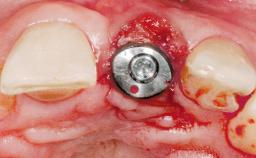

Late Placement of an Implant in a Maxillary Left Central Incisor Site

A 30-year-old female patient had lost tooth 21 and was referred to our clinic for consultation and treatment. Due to advanced apical infection, tooth 21 had been extracted two months earlier at another clinic and an acrylic-resin tooth had been bonded to the adjacent teeth. The patient desired implant treatment to avoid any damage to the adjacent natural teeth. While the patient had no history of any systemic disorder, she was a heavy smoker and exhibited medium to advanced periodontitis in the entire jaw. After the initial treatment to achieve a pocket probing depth of less than 4 mm and no bleeding on probing, a decrease in the height of the papillae mesial and distal to the extraction site and overall gingival recession were observed.

Type of Implants One-Piece|Reduced-Diameter